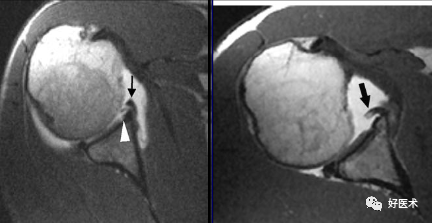

2)部分撕裂

-

肌腱增厚、变薄、不规则;

肌腱的关节面或滑膜面撕裂,或肌腱内分离缺损,肌腱连续性存在;

斜冠面T1WI 上呈低至中等信号强度,PDWI呈中等到高信号,T2WI +FS上呈高信号强度;

3)完全性撕裂

原发征象:肌腱局部缺如,连续性液体信号横贯肌腱的全层,这使得盂肱关节和肩峰下滑囊相通。